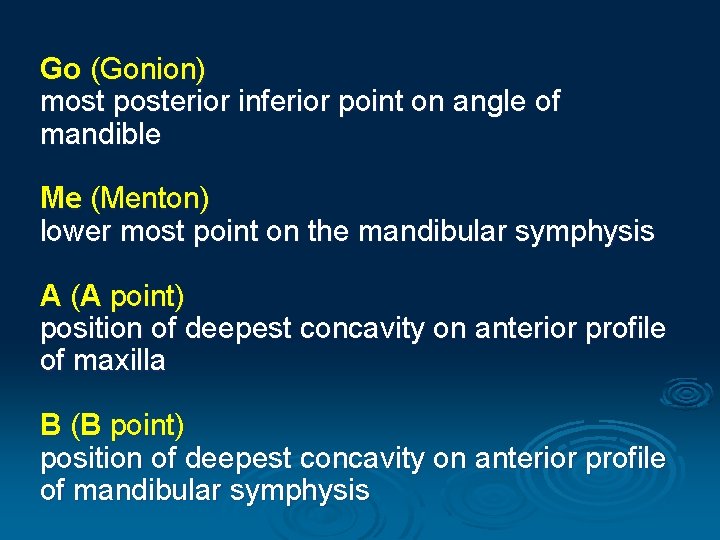

Go (Gonion) most posterior inferior point on angle of mandible Me (Menton) lower most point on the mandibular symphysis A (A point) position of deepest concavity on anterior profile of maxilla B (B point) position of deepest concavity on anterior profile of mandibular symphysis